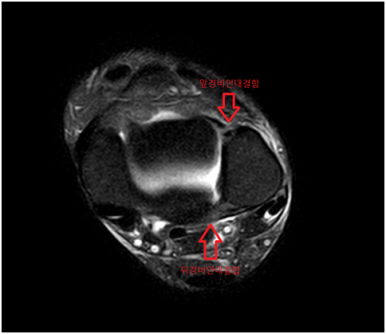

발목 MRI에서 바깥쪽 인대를 구성하는 전거비인대, 후거비인대에 심한 손상, 안쪽 인대를 구성하는 삼각인대 손상, 발목 경비인대결합 손상으로 수술이 가능한 정형외과 병원으로 전원하였습니다.

• MRI 검사: 인대 손상 MRI 검사: 인대 손상